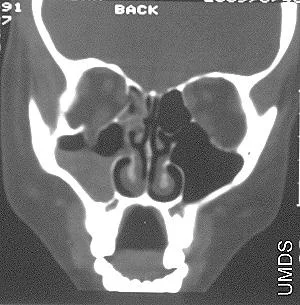

Left/Right Orbital Cellulitis

Can be from Paranasal sinusitis

Investigations: (to exclude orbital causes - tumors, abscess…)

- CT with contrast

- MRI (may be used if CT is inconclusive, or to better evaluate soft tissues/brain involvement).